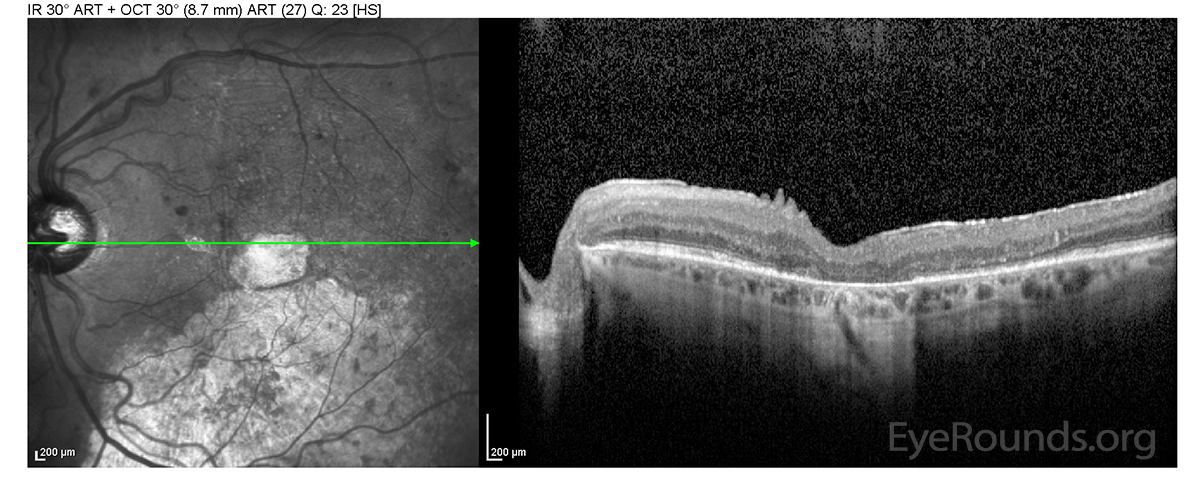

Figure 2. Optical coherence tomography (OCT): 1 year after initial presentation

There is a large fovea-involving, serous macular detachment with pockets of overlying intraretinal fluid.

OD: There is a large fovea-involving, serous macular detachment with pockets of overlying intraretinal fluid.

There is a moderately sized fovea-involving, serous macular detachment with minimal intraretinal fluid.

OS: There is a moderately sized fovea-involving, serous macular detachment with minimal intraretinal fluid.